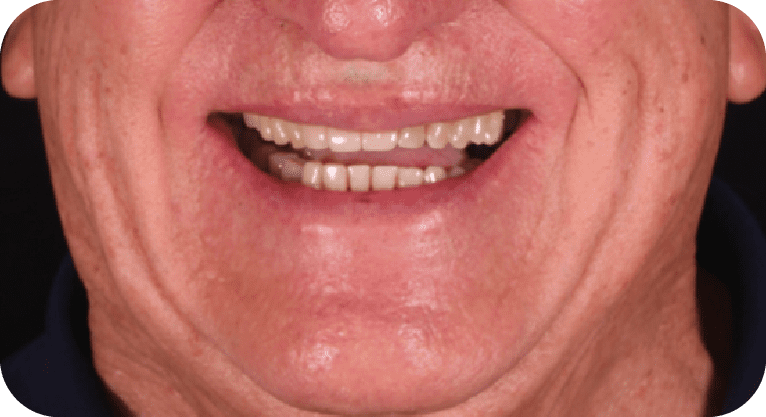

Female patient, “42” years old

Treatment: Dental implant

The patient was dissatisfied with the short appearance of his teeth, so a periodontal gingival reshaping surgery was performed to recontour the gum tissue and expose more tooth surface. This achieved a more harmonious tooth-gum proportion and significantly improved the aesthetics of his smile.